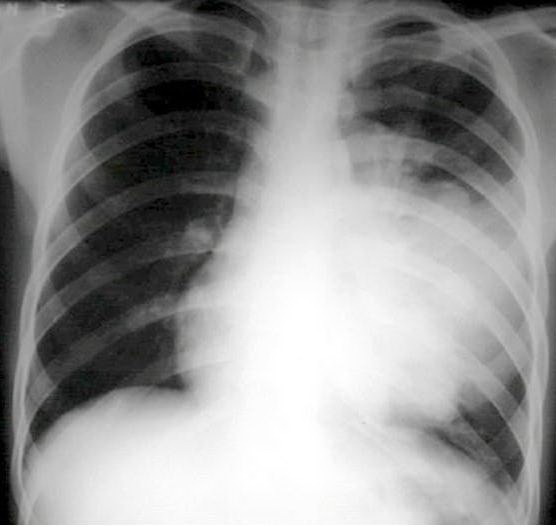

Dấu hiệu X

quang: thấy một đám mờ của một thùy hay một phân thùy, có hình tam giác đáy

quay ra ngoài, đỉnh quay vào trong, có thể thấy hình ảnh tràn dịch màng phổi hoặc

hình rãnh liên thuỳ. Chụp CT Scan phổi độ phân giải cao có thể được chỉ định

trên những bệnh nhân có các dấu hiệu lâm sàng của viêm phổi nhưng không thấy

hình ảnh bất thường trên phim X quang phổi, giúp quan sát được các tổn thương

nhỏ, ở vị trí khó thấy như gần rãnh cột sống, hoặc các tổn thương kẽ như dạng

kính mờ lúc còn ít.

X quang phổi chuẩn: có hội chứng lấp đầy phế nang, có thể có hình ảnh tràn

dịch màng phổi hoặc hình rãnh liên thuỳ dày. Các tổn thương dạng lưới nốt, hình

kính mờ gợi ý viêm phổi do vi khuẩn không điển hình (do Mycoplasma pneumoniae,

Chlamydia pneumoniae, Rickettsia pneumoniae). Tuy nhiên hình ảnh X quang không đặc

hiệu cho căn nguyên.